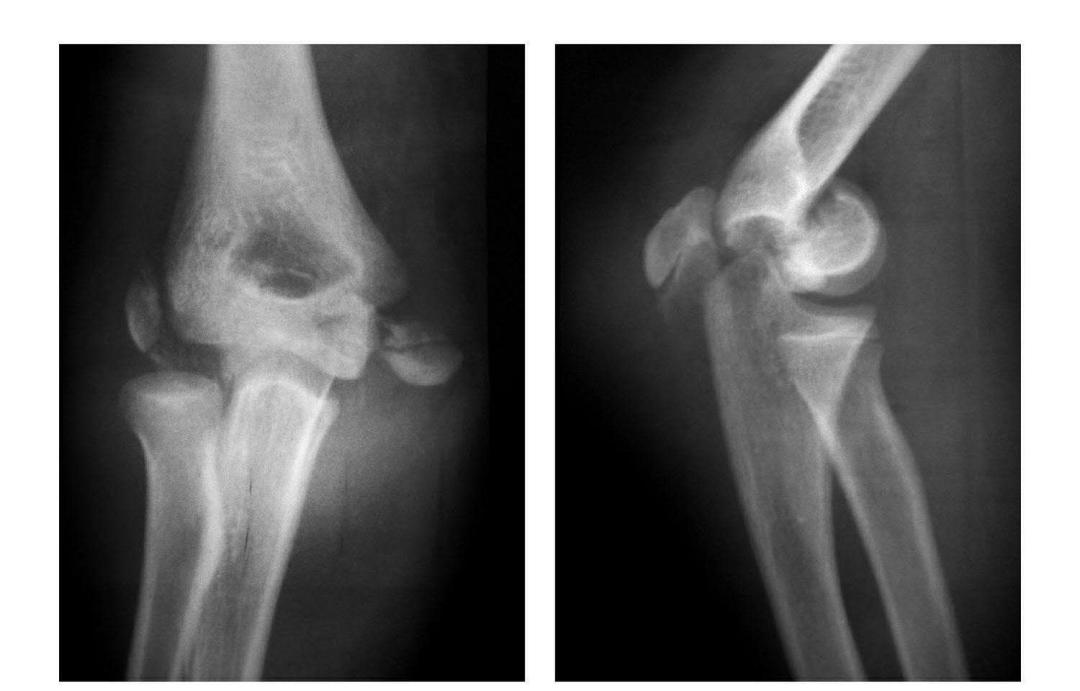

本病文献未见报道,即肱骨小头中部呈前后(矢状面)纵向骨折,将小头分为内外两部分。

例:肱骨小头矢状面骨折,折线波及外髁皮质骨折片,并鹰嘴突无移位骨折。